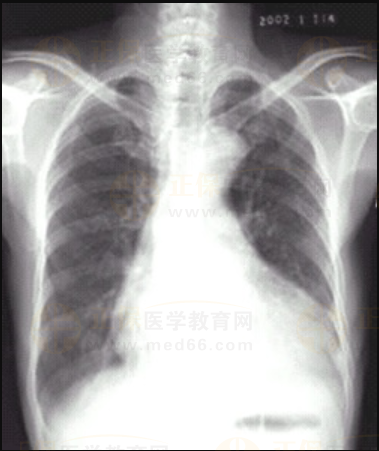

03卷-4.病史:女性,73歲,血壓升高10年,心悸、頭暈、乏力2周。診斷

A.梨形心

B.靴形心

C.普大型心臟

D.正常心臟

【該題針對(duì)“ X線-心臟增大(二尖瓣型、主動(dòng)脈型和普大型) ”知識(shí)點(diǎn)進(jìn)行考核】